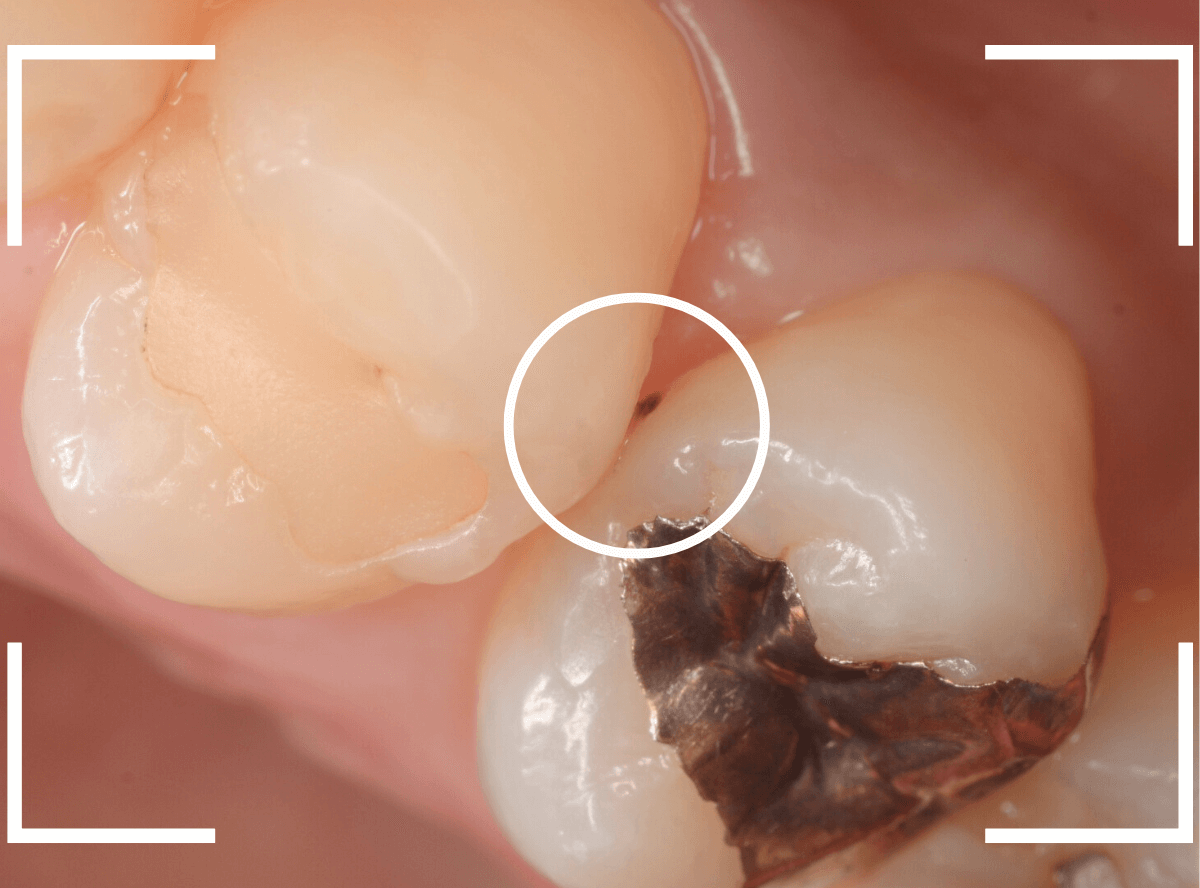

Case.12 金属のつめものの下の状況がわからない

定期メンテナンスに通っていらっしゃっている患者さんです。

金属のつめものが若干不適合気味になっているのと、その周りが黒くぼやっとなっていて怪しいですが、金属色が透けているのか虫歯になり始めてるのか、よくわかりません。

レントゲン写真で確認します。

虫歯があるのかはっきりしない写り方です。

患者さんに状況を説明の上、つめものを外して調べてみる事にしました。

つめものを外すと、虫歯が出てきました。

金属のつめものの下に、アマルガムという金属がつめてあるのも見られます。

あとは、少しずつ削りながら、虫歯を調べます。

全ての虫歯を除去しました。

幸い、あまり大きく歯を削らずに済みました。

早いうちに治療が出来てよかったかと思います。